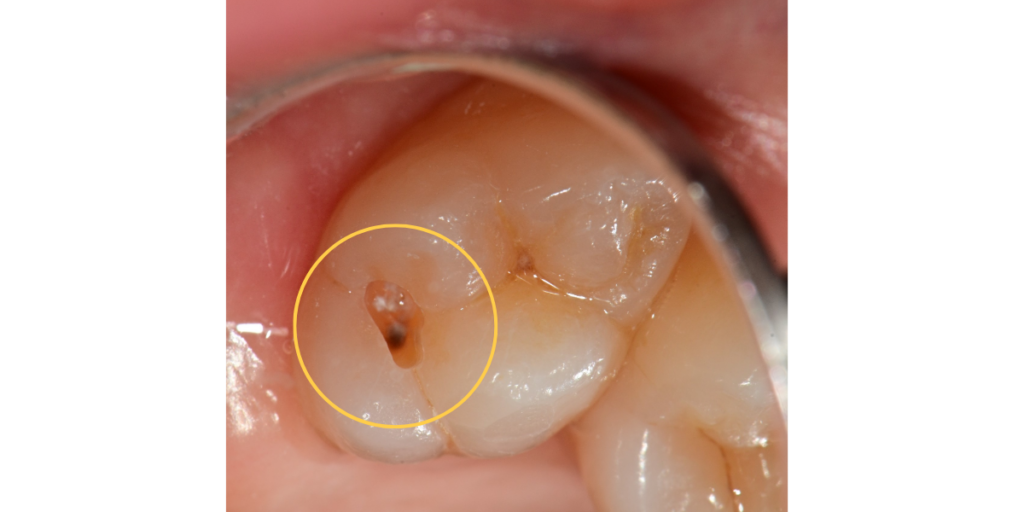

치료 후 2026.02.25

노원역치과 치료 결과, 어두웠던 충치 부위가 깨끗하게 제거되었으며

레진을 통해 치아 본연의 색상과 형태가 자연스럽게 복구되었습니다.

점 상태의 충치가 말끔히 해결됨으로써 향후 발생할 수 있었던

심한 통증이나 신경 손상의 위험을 사전에 차단할 수 있었습니다.

이번 치료의 핵심은 정기검진을 통해 적절한 시기에 문제를 발견하여 치아 삭제량을 줄이고

레진이라는 재료를 통해 심미성과 기능을 동시에 회복한 데 있습니다.